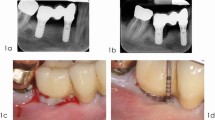

Based on the techniques and factors discussed in the previous sections, we propose a decision tree to guide clinicians in selecting the most appropriate surgical approach for PIKM augmentation. This framework integrates considerations such as the residual width of KM and implant position, aiming to simplify clinical decision-making and enhance treatment outcomes. By addressing these variables systematically, the decision tree assists clinicians in tailoring surgical strategies to individual patient needs, ensuring predictable results and minimizing complications (Fig. 1).